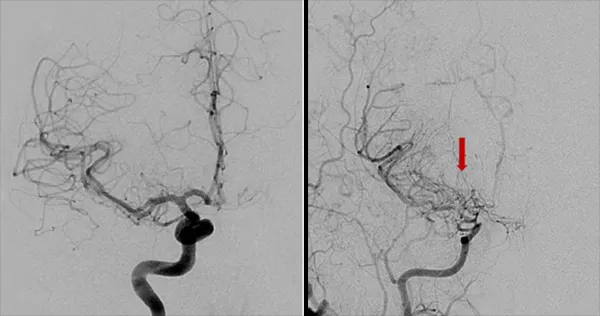

这些代偿机制之一是侧支循环的形成,即附近的血管生成小分支来供应血液不足的区域。在脑血管造影中,这些侧支血管形成的异常血管网状结构呈现出一种模糊的特征,类似于烟雾,因此这种疾病被形象地命名为“烟雾病”,在日语中的意思为“一股烟”。

烟雾病(Moyamoya Disease,简称MMD)是一种罕见的慢性脑血管疾病。当医生们在进行脑血管造影检查时,发现患者脑底部形成的异常血管网在影像上呈现出袅袅升起的烟雾状,因此得名。

DSA被认为是诊断烟雾病的“金标准”。通过将造影剂注入血管,并进行X射线成像,DSA可以清晰地显示血管的狭窄、闭塞和异常血管网。